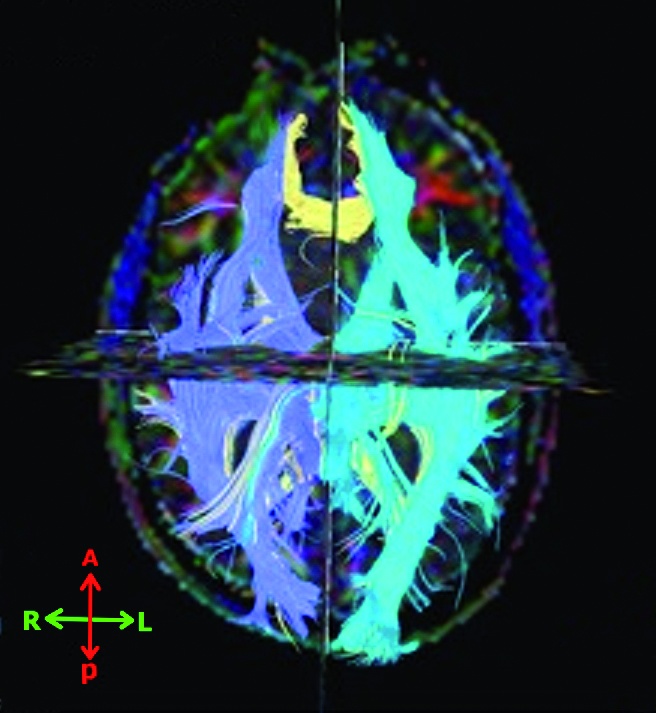

Im Einzelfall können die Veränderungen des Gehirns diskret sein, so dass es spezieller kernspintomographischer Techniken bedarf, um sie zu erkennen. Das normale Computertomogram ist bei einem “reinen“ mTBI mit oder ohne Blast-Verletzung immer normal. Mikroblutungen sind in T2*-gewichteten Kernspintomografie-Bildern zu sehen, Läsionen der weißen Substanz, sofern sie in den gängigen T1/T2/FLAIR/DWI-Wichtungen nicht zu erkennen sind, im “Diffusion Tensor Imaging“ (DTI) [4].

Das DTI-Verfahren erscheint als besonders aussichtsreich (Beispiel siehe Abbildung 1). Die geschädigten Axone geben keine Diffusionsrichtung mehr vor (Anisotropie), die mittels DTI visualisiert werden kann. Man weiß, dass die Anisotropie sowohl im akuten wie im chronischen Stadium mit kognitiver Beeinträchtigung assoziiert ist. Als besonders vulnerabel gelten die Kommissuren, bei denen die weißen Fasern dicht gepackt sind, so der hintere Teil des Balkens. Es gibt aber noch keine Normwerte, so dass das Verfahren noch nicht breit eingesetzt werden kann. Zum jetzigen Zeitpunkt kann es deshalb nicht als etabliert gelten.

Bildquelle: Abbildung 1: BwKrhs Ulm – Radiologische Abteilung

Abb. 1: Beispiel für Diffusion Tensor Imaging

Darstellung der Faserbündel; gleiche Faserbündel haben gleiche Farben.